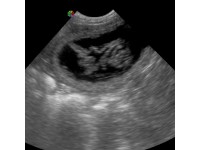

One of the most common questions asked of ultrasound technicians performing pregnancy scans – particularly on dogs – is the due date. In breeds where parturition can be difficult, it is important to know when the bitch is due so that the owner can be present, or arrangements for a Caesarean section be made in advance.

CANINE AND FELINE PREGNANCY – HOW ULTRASOUND CAN HELP

As with any pregnancy, an expectant mother of the veterinary world should ideally minimise the number and type of stressors they may be exposed to in order to increase the chance of their offspring having calm and relaxed natures.